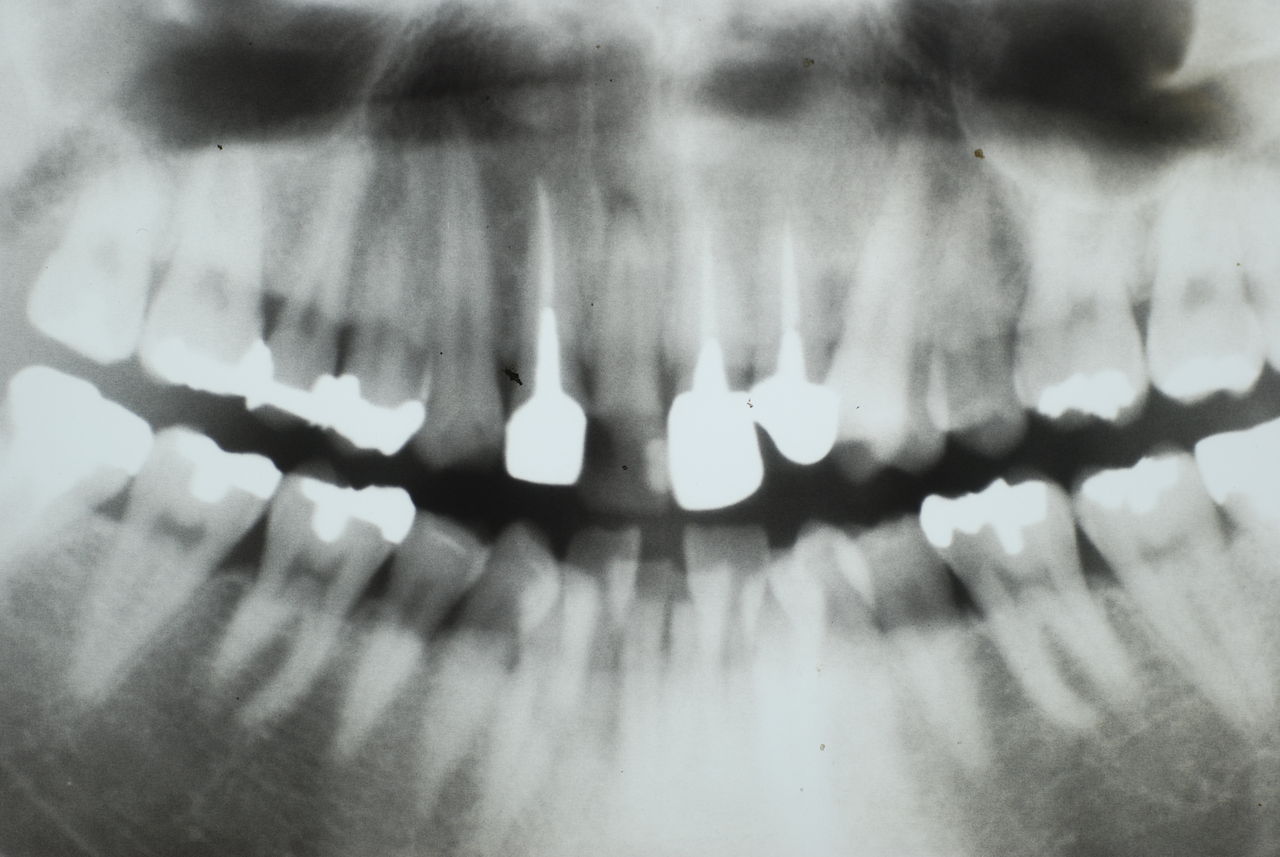

歯周病の疑いで東京のかなり遠方の方が来院されました。

驚くべきことですが、定期検診は受けていたそうです。しかしながら歯周病の指摘は受けたことがないそうです。

何故か?定期検診が虫歯のチェックのみになり、又肝心の歯周病の検査や歯周病の部分の予防や治療のためのブラシの使い方などを学んだ事がないのです。